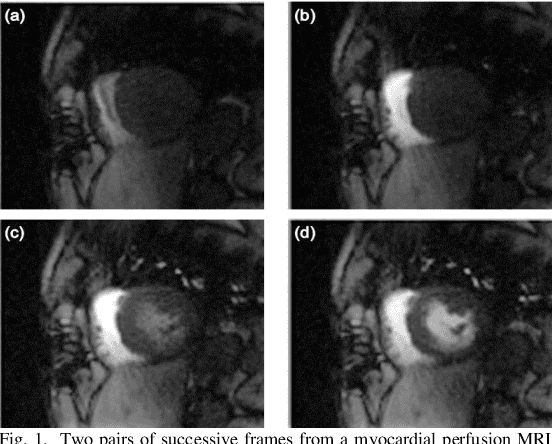

Abstract:Coronary artery disease (CAD) remains the world's leading cause of mortality and the disease burden is continually expanding as the population ages. Recently, the MR-INFORM randomised trial has demonstrated that the management of patients with stable CAD can be guided by stress perfusion cardiovascular magnetic resonance (CMR) imaging and it is non-inferior to the using the invasive reference standard of fractional flow reserve. The benefits of using stress perfusion CMR include that it is non-invasive and significantly reduces the number of unnecessary coronary revascularisations. As compared to other ischaemia tests, it boasts a high spatial resolution and does not expose the patient to ionising radiation. However, the main limitation of stress perfusion CMR is that the diagnostic accuracy is highly dependent on the level of training of the operator, resulting in the test only being performed routinely in experienced tertiary centres. The clinical translation of stress perfusion CMR would be greatly aided by a fully automated, user-independent, quantitative evaluation of myocardial blood flow. This thesis presents major steps towards this goal: robust motion correction, automated image processing, reliable quantitative modelling, and thorough validation. The motion correction scheme makes use of data decomposition techniques, such as robust principal component analysis, to mitigate the difficulties in image registration caused by the dynamic contrast enhancement. The motion corrected image series are input to a processing pipeline which leverages the recent advances in image processing facilitated by deep learning. The pipeline utilises convolutional neural networks to perform a series of computer vision tasks including myocardial segmentation and right ventricular insertion point detection...